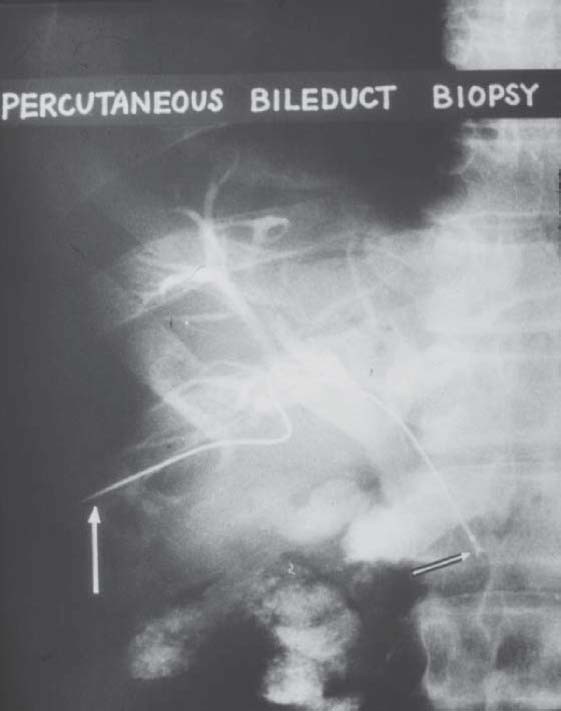

Fig. 6

figure 6

The first case of percutaneous transhepatic bile duct biopsy in the world. This is a case of recurrent gastric cancer combined with obstructive jaundice. The bile cytology showed that it was Class 1 but the result of biopsy exactly revealed the existence of cancer cells in tissues under the epithelium of the bile duct